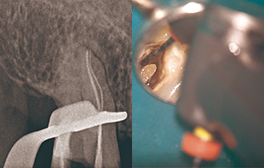

• EDGE ENDO®を使用した臨床例

• Edge GlidePath™、EdgeTaper Platinum™、EdgeSequel Sapphire™を使用して二重湾曲根管の形状を残したまま、根管形成を行った例。

エッジグライドパスを使用

Edge GlidePath™

エッジテーパープラチナムを使用

EdgeTaper Platinum™ in MB

XPエンドシェイパーとエッジシークエルサファイアを使用

XP-Endo Shaper(白水貿易)+EdgeSequel Sapphire™ in MB1 & MB2

エッジシークエルサファイアを使用

#35/.04 EdgeSequel Sapphire™